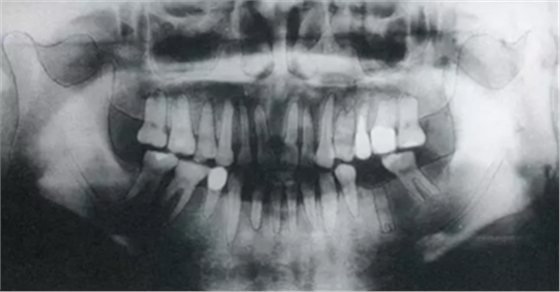

▲圖6-1

頰側(cè)角化齦較少,頰系帶高位附著。

▲圖6-2

同時期的曲面斷層片。

▲圖6-3

種植體植入后的X光片